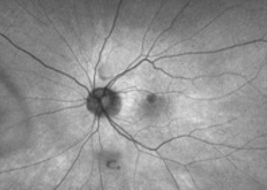

Multifocal lesions often grow faster than unifocal lesions6

Extrafoveal lesions often progress faster than foveal lesions6

Hyperfluorescence on FAF imaging is often correlated with faster lesion progression6